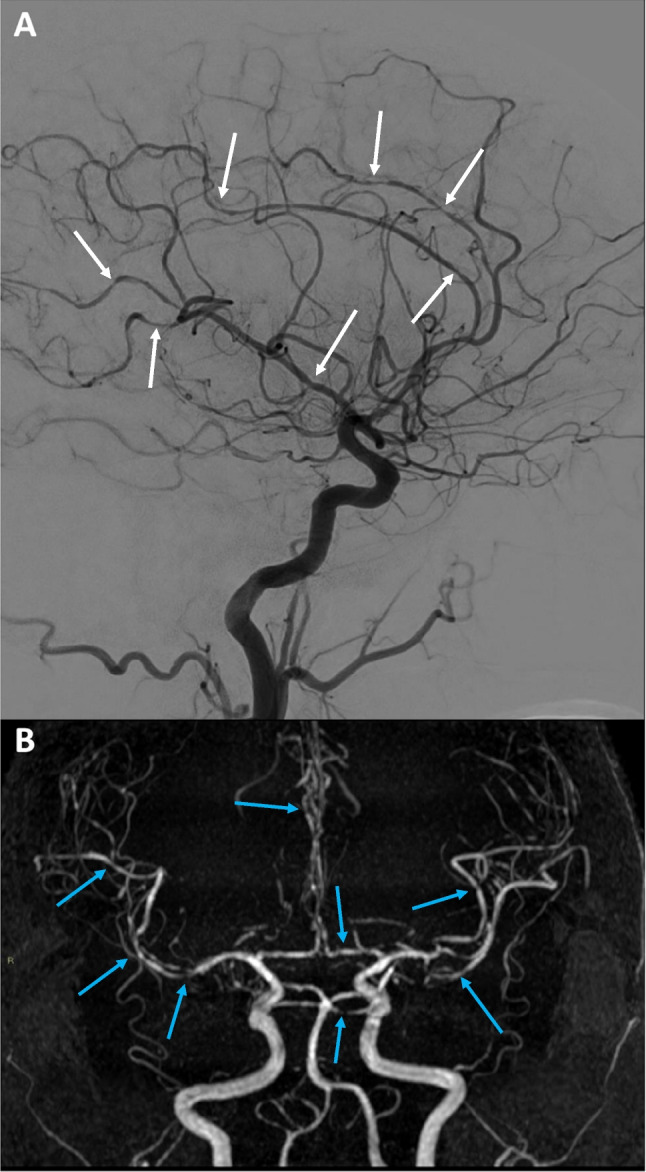

A transcranial color-coded Doppler (TCCD) performed on the same day showed diffuse bilateral multifocal blood flow acceleration in all principal intracranial vessels, especially in the right hemisphere, with focal aliasing at color-Doppler signal and low flow turbulences (Fig. 1). Lindegaard index was greater than 7 on the right and 4.5 on the left side, indicating vasospasm. Interestingly, the greater involvement of right ACM M1 and M2 segments at TCCD was consistent with clinical (left hemiparesis) and brain magnetic resonance imaging (MRI) (subarachnoid haemorrhage (SSH) at right cortical frontal convexity).

Fig. 1.

Transcranial color-coded Doppler (TCCD) images showing focal acceleration, diffuse aliasing, and flow turbulence in the principal intracranial vessels. A Right distal middle cerebral artery (M1) with peak systolic velocity (PSV) of ≈ 380 cm/s, B right posterior cerebral artery (P1) with PSV ≈ 300 cm/s, and C basilar artery with PSV ≈ 180 cm/s and flow turbulence

Laboratory investigations for autoimmune disease were all normal. Subsequently performed brain MRI and MR angiogram (MRA) documented diffuse and multifocal narrowing and irregularities of intracranial vessels (Fig. 2). A thin cortical convexity SAH and two restricted-diffusion areas indicating small recent ischemic lesions were also detected with MRI.

Fig. 2.

Cerebral angiography (A) and magnetic resonance angiography (MRA) (B) depicting remarkable smooth multifocal widespread narrowing and irregularities in the vessels of both anterior and posterior intracranial circulation

Finally, digital subtraction angiography (DSA) was compatible with multifocal vasoconstriction of middle, anterior, pericallosal, and posterior cerebral arteries of both sides (Fig. 2), while vascular malformations or saccular aneurysms were ruled out. Based on clinical history and instrumental findings, a diagnosis of reversible cerebral vasoconstriction syndrome (RCVS) was made.